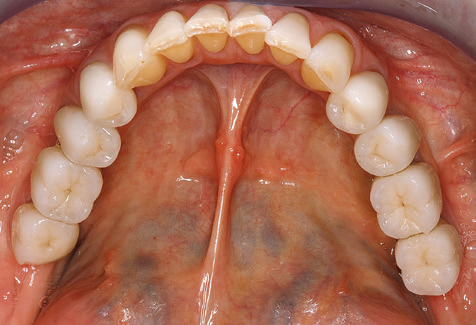

Due to the presence of periodontal disease, SPT was performed every three months in the first years following the insertion. The patient demonstrated a high degree of motivation and good compliance. The pocket depths recorded annually revealed a stable periodontal situation with a BOP index of below five per cent. On the basis of the stable periodontal situation and good cooperation on the patient’s part, the recall interval was extended to every six months as of the sixth year of the prosthetic function phase. Following the change in the recall interval, the respective annual documentation of the periodontal status continued to reveal a stable periodontal situation with no increase in the pocket depths and a BOP index below five per cent (Fig. 2a and b).

Fig. 2: The pocket depths recorded annually with six-monthly SPT display no increasing trend and a BOP index of below 5 per cent with a largely inflammation-free periodontal situation. a) PERIO status in 2011 (after five years with implants). b) PERIO status in 2016 (after ten years with implants).